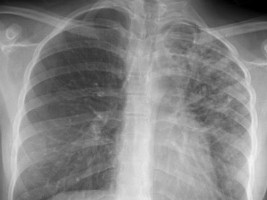

Haïti - Santé : Le pays à le plus haut taux de tuberculose des Amériques

Malgré les nombreux efforts du Gouvernement haïtien pour faire reculer la tuberculose dont entre autres la gratuité de la prise en charge des patients dans 256 centres spécialisés financés par le Trésor Public. En 2012, il y avait 212 cas pour 100,000 habitants (Source PNUD), en 2016 on en comptait 194 sur 100,000, Haïti reste le pays qui présente l’incidence la plus élevée des Amériques (près de 17,000 cas dépistés en 2013 chez des patients âgés de 15 à 34 ans)...

La tuberculose est une maladie très contagieuse causé par une bactérie « Mycobacterium tuberculosis » qui touche le plus souvent les voies respiratoires. C’est une maladie que l’on peut éviter et soigner. La tuberculose se transmet d’une personne à l’autre par voie aérienne. Quand une personne atteinte de tuberculose tousse, éternue ou crache, elle projette des bacilles tuberculeux dans l’air, il suffit d’en inhaler quelques-uns pour être à son tour infecté.